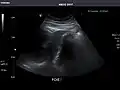

Spleen: Normal in size.

Spleen -